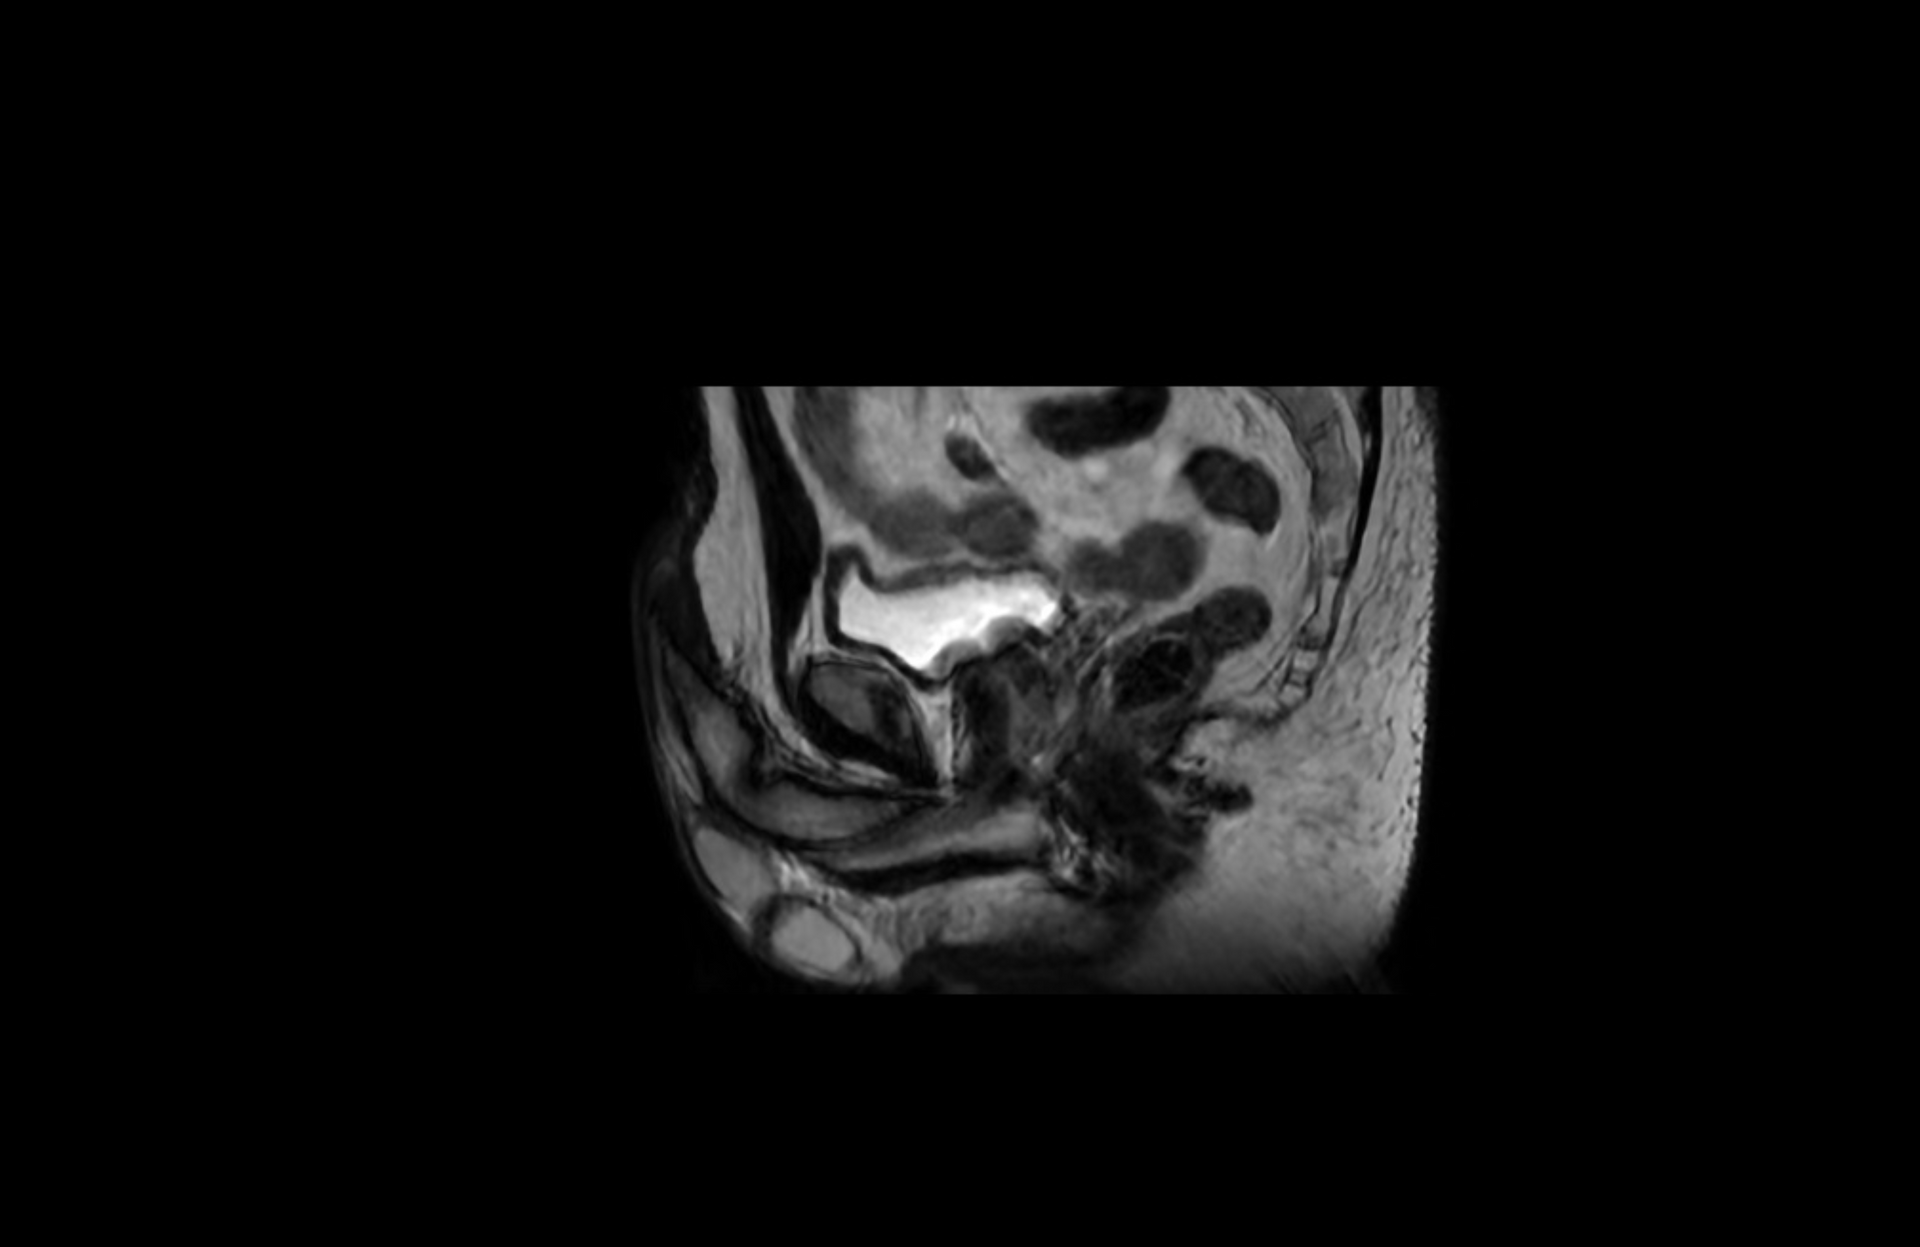

IRM pénienne ou de la verge

L’IRM pénienne permet une exploration de la verge. Elle est surtout prescrite dans le cadre d'une maladie de Lapeyronie ou en post traumatique.

Une injection d’un produit de contraste est classiquement injecté permettant de détecter des plaques de Lapeyronie actives.